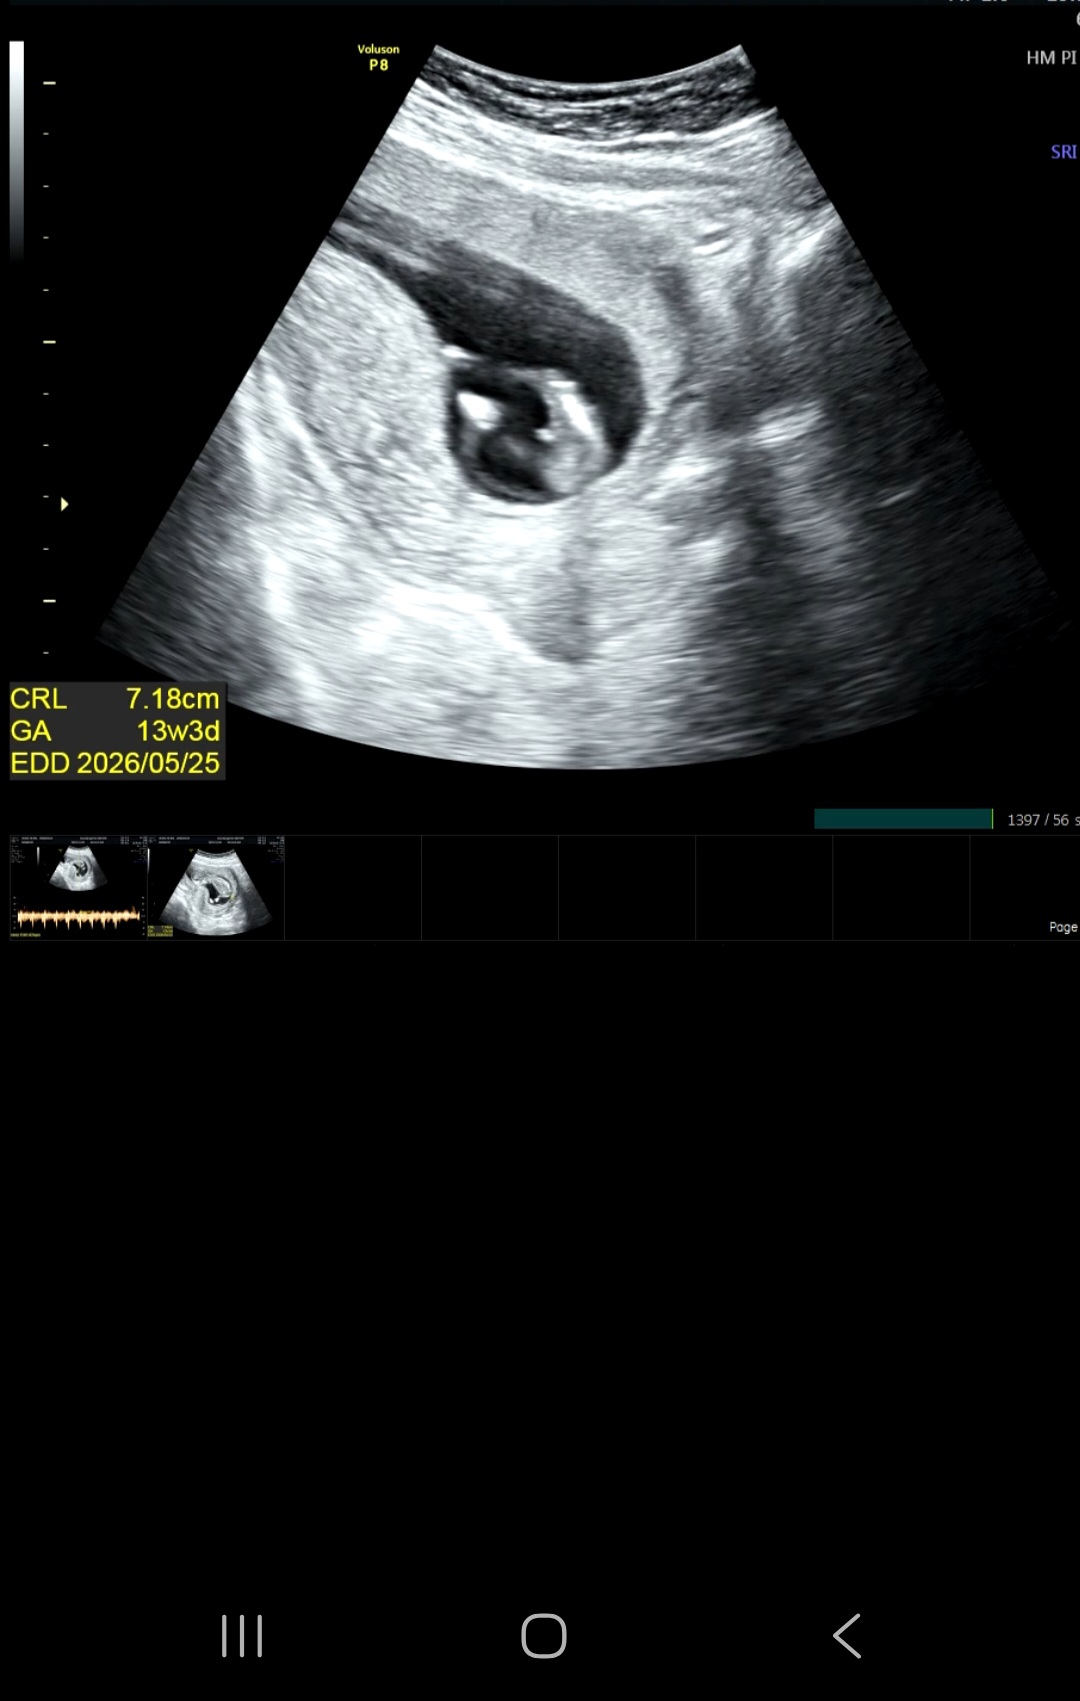

이게 뭘까요...??..

갑자기 안 보이다가 마지막에 가운데가 딱..! 보이는 순간 탯줄일까요?! 아닐까요?! 아직 성별은 몰라요...